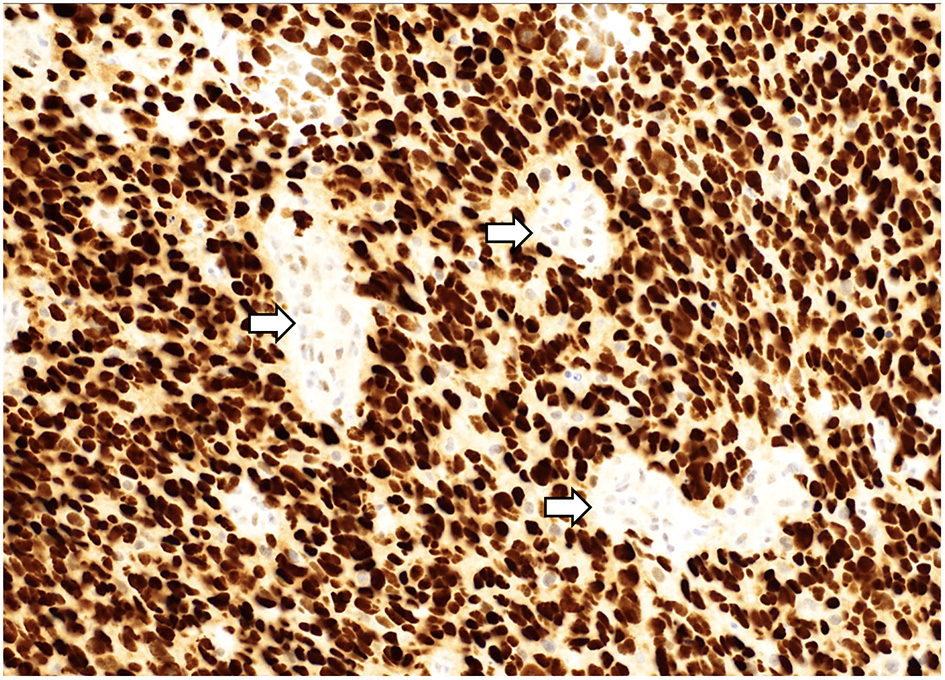

Figure 4

A “glioblastoma” with a mutation in TP53 demonstrating strong, diffuse nuclear staining for p53 with wildtype staining present in vessels (arrows). p53 immunostain, 200x magnification.

Mutations in histone genes are the most common molecular findings in pediatric HGGs with H3 K27M mutations associated with midline tumors (Figures 5, 6) and H3 p.G34R/V mutations occurring in hemispheric tumors. The majority of these tumors are histologically high-grade; however, it should be noted that infiltrative, astrocytic tumors of the midline with H3 K27M mutations are classified as “diffuse midline gliomas,” and regardless of histologic grade, correspond to WHO grade 4 (19). In addition, co-occurring mutations in TP53 (Figure 4) and ATRX (Figure 7) may be seen in tumors with H3 mutations, whereas IDH mutations are not observed (24, 25). Of note, circumscribed/non-diffuse gliomas of the midline are not considered grade 4, according to the (WHO/CNS/5) (26). Diffuse midline gliomas are not the primary focus of this paper.